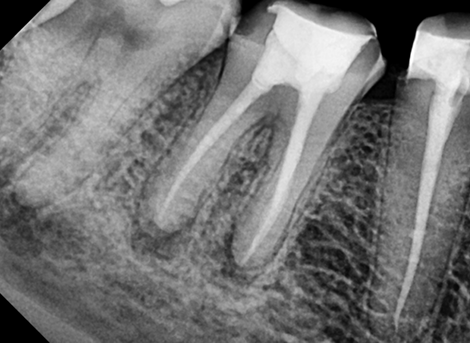

Complete disinfection of the root canal.

Sealing the Canal